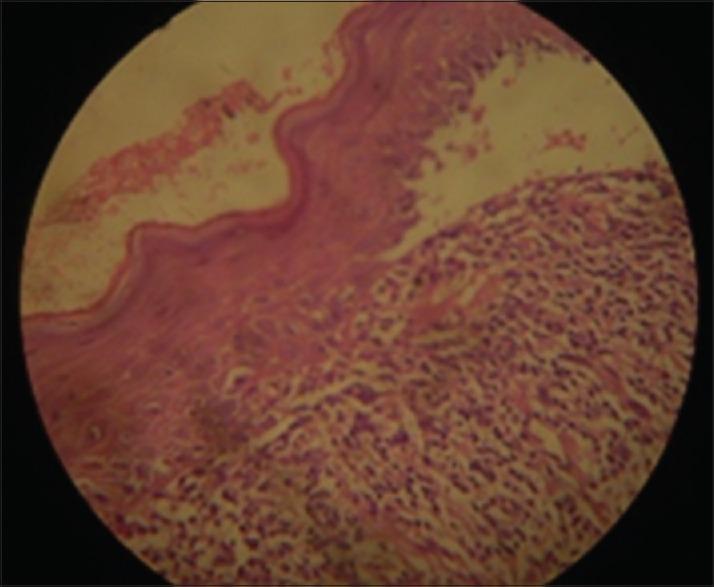

Lichen planus (LP) is a potentially malignant disorder with an immune-mediated etiopathogenesis. The condition frequently affects the skin, oral mucosa, skin appendages, and other mucous membranes. Oral lesions usually precede the onset of skin lesions and in majority of cases may only be presenting symptom. Isolated LP of the lip is rarely encountered in the clinical practice and is usually seen along with skin/other mucous membrane involvement. The clinical appearance poses diagnostic dilemmas and is often misinterpreted. This case report aims to highlight an interesting case of LP of the lower lip in a 50-year-old male patient. The patient presented with a diffuse erosive lesion on the lower lip bordered by white radiating striae on its inner aspect. Histopathological and immunofluorescent studies confirmed LP of the lip. Topical corticosteroids and Vaseline lip therapy were prescribed to the patient. There was considerable healing in the lip lesion during the follow-up period. However, recurrence was noted in the left buccal mucosa.

扁平苔藓(LP)是一种具有免疫介导发病机制的潜在恶性疾病。该病常累及皮肤、口腔黏膜、皮肤附属器及其他黏膜。口腔病变通常先于皮肤病变出现,且在大多数情况下可能是唯一的症状表现。临床实践中很少遇到孤立的唇部扁平苔藓,通常与皮肤/其他黏膜受累同时出现。其临床表现会造成诊断上的难题,且常被误诊。本病例报告旨在突出一名50岁男性患者下唇扁平苔藓的有趣病例。该患者下唇出现弥漫性糜烂性病变,内缘有白色放射状条纹。组织病理学和免疫荧光研究证实为唇部扁平苔藓。给患者开了外用皮质类固醇和凡士林唇部治疗。随访期间唇部病变有明显愈合。然而,左侧颊黏膜出现了复发。